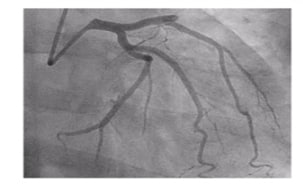

1 Acute coronary syndrome with

ST-segment elevation and coronary

syndrome without ST-segment elevation

2 Acute myocardial injury without vascular atherosclerosis